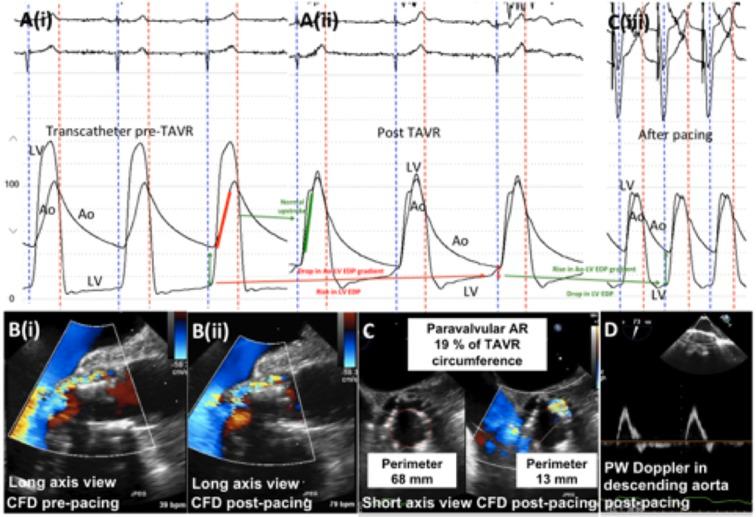

Transcatheter aortic valve replacement (TAVR) has become the preferred therapy for treatment of severe aortic stenosis in patients at intermediate to high risk of perioperative mortality following surgical aortic valve replacement. Haemodynamic assessment is an integral part of the procedure, and it is crucial for the operator to have an in-depth understanding of the haemodynamic alterations that occur during balloon aortic valvuloplasty and transcatheter valve deployment. Comprehension of the haemodynamic tracings is also pivotal for early recognition of periprocedural complications. With expanding indications for TAVR, it is imperative for members of the structural heart team to have an in-depth, nuanced understanding of transcatheter haemodynamic waveforms and their correlation with echocardiographic Doppler waveforms that are obtained periprocedurally during TAVR. This review provides a collection of transcatheter haemodynamic tracings and their corresponding Doppler echocardiography correlates that are demonstrative of physiological alterations and pathological lesions (complications) that occur during TAVR.